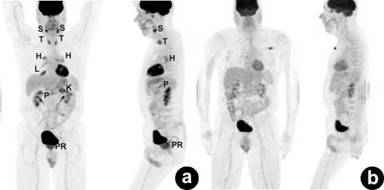

Figure 4. Serial PET coronal maximum intensity projection (MIP) shows pre-corticotherapy (a.) and 1-month post-corticotherapy with resolution of all hypermetabolic IgG4-related lesions (b.). Case#1. 1: salivary glands; 2: bilateral peri-hilar regions; 3: bilateral lower lungs; 4: pancreas; 5: porta-hepatitis/common bile duct; 6: gallbladder; 7: abdominal aorta |

Figure 11. Serial coronal and sagittal pre- (a.) and post-corticotherapeutic (b.) PET maximum intensity projection (MIP) images show complete resolution of the diffuse hypermetabolic lesions of systemic IgG4-related sclerosing disease. The focus at the left upper anterior chest wall represents an artifact (b.). Case#2. S: salivary glands; T: thyroid gland; H: bilateral hilar nodes; L: right middle pulmonary lobe; K: upper pole of the left kidney; P: pancreas; PR prostate |

Most patients with autoimmune pancreatitis have elevated IgG and IgG4 levels. In 2001, Hamano et al. demonstrated that IgG4 is more than sensitive than total IgG for diagnosing autoimmune pancreatitis [22]. The sensitivity and specificity of elevated IgG4 (cut-off: 135 mg/dL) for diagnosing autoimmune pancreatitis are approximately 70% and 90%, respectively [23, 24, 25]. In addition, Hamano et al. also showed that serum IgG4 in patients with autoimmune pancreatitis decreased after one month of corticotherapy [22]. This was not observed in Case #1. Prior to steroid treatment, IgG4 was 41.2 mg/dL; however, after one month of corticotherapy, it increased to 546 mg/dL. Only IgG decreased from 2,430 mg/dL to 1,310 mg/dL. One possible explanation of the difference between our observation and that of Hamano et al. is that the authors compared IgG4 levels of pre- and post-corticotherapy in only 12 out of 20 patients with autoimmune pancreatitis [22]. Our result seems to support the conclusion of a meta-analysis on the utility of IgG4 in follow-up autoimmune pancreatitis post steroid therapy. IgG4 is useful in therapeutic monitoring only when the IgG4 level of pre-corticotherapy is high [26]. Despite elevated IgG4 during post-corticotherapy, PET/CT is valuable in demonstrating resolution of IgG4-related lesions (Figure 4). After reviewing records from the outside, we noticed that serum IgG and IgG4 levels were not measured in cases where systemic IgG4-related sclerosing disease was confirmed by immunohistopathology (Cases #2 and #3). Clinicians should be aware of this new entity because corticosteroid is the treatment of choice, not invasive surgery.

Corticosteroid is the treatment of choice for patients with systemic IgG4-related sclerosing disease. The response to steroid was incorporated in the American, Japanese, and Korean diagnostic criteria of autoimmune pancreatitis [18]. However, there is no consensus on the standard regimen or duration of corticotherapy. Normally, prednisolone (30-40 mg/day) is initiated and tapered by 5 mg every 2-4 weeks [16]. Because of the ability of PET/CT to image the whole body, it is a valuable tool for monitoring therapy and demonstrating sites of relapse or flare-up as seen in Figures 4 and 10.